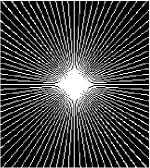

All the experiments are implemented on a Windows workstation with Intel Core i9 CPU at 3.3GHz and an Nvidia GTX-1080Ti GPU with 11GB of graphics card memory via TensorFlow Abadi et al. (2016). The parameters in the proposed network are initialized by using Xavier initialization Glorot and Bengio (2010). We trained the meta-learning network with four tasks synergistically associated with four different CS ratios: 10%, 20%, 30%, and 40%, and test the well-trained model on the testing dataset with the same masks of these four ratios. We have 300 training data for each CS ratio, which amount to total of 1200 images in the training dataset. The results for and MR reconstructions are shown in Tables 5.4 and 5.4 respectively. The associated reconstructed images are displayed in Figures 1 and 3. We also test the well-trained meta-learning model on unseen tasks with radio masks for skewed ratios: 15%, 25%, 35%, and random Cartesian masks with ratios 10%, 20%, 30% and 40%. The task-specific parameter for the unseen tasks are retrained for different masks with different sampling ratios individually with fixed task-invariant parameters . In this experiments, we only need to learn for three skewed CS ratios with radio mask and four regular CS ratios with Cartesian masks. The experimental training proceed on less data and iterations, where we performed on 100 MR images with 50 epochs. For example, for reconstructing MR images with CS ratio 15% radio mask, we fix the parameter and retrain the task-specific parameter on 100 raw data with 50 epochs, then test with renewed on our testing data set with raw measurement that sampled from radio mask with CS ratio 15%. The results associated with radio masks are shown in Table 5.4 and 5.4, Figure 2 and 4 for and images respectively. The results associated with Cartesian masks are list in Table 5.4 and reconstructed images are displayed in Figure 5.

In general supervised learning, training data need to be in the same or similar distribution, heterogeneous data exhibits different structure variations of features which hinders CNNs to extract features efficiently. In our experiments, raw measurements sampled from different ratios of compressed sensing display different levels of incompleteness, these undersampled measurements do not fall in the same distribution but they are related. Different sampling masks are shown at the bottom of Figure 1 and 2 may have complemented sampled points, in the sense that some of the points which sampling ratio mask does not sample have been captured by other masks. In our experiment, different sampling masks provide their own information from their sampled points so that four reconstruction tasks help each other to achieve an efficient performance. Therefore, it explains the reason that Meta-learning is still superior to conventional learning when the sampling ratio is large.